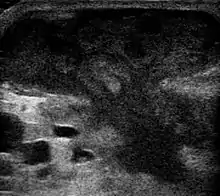

They are usually caused by a bacterial infection.[8] Often many different types of bacteria are involved in a single infection.[6] In the United States and many other areas of the world the most common bacteria present is methicillin-resistant Staphylococcus aureus.[1] Rarely, parasites can cause abscesses; this is more common in the developing world.[3] Diagnosis of a skin abscess is usually made based on what it looks like and is confirmed by cutting it open.[1] Ultrasound imaging may be useful in cases in which the diagnosis is not clear.[1] In abscesses around the anus, computer tomography (CT) may be important to look for deeper infection.[3]

An abscess is a localized collection of pus (purulent inflammatory tissue) caused by suppuration buried in a tissue, an organ, or a confined space, lined by the pyogenic membrane.[21] Ultrasound imaging in the emergency department can help in a diagnosis.[22]